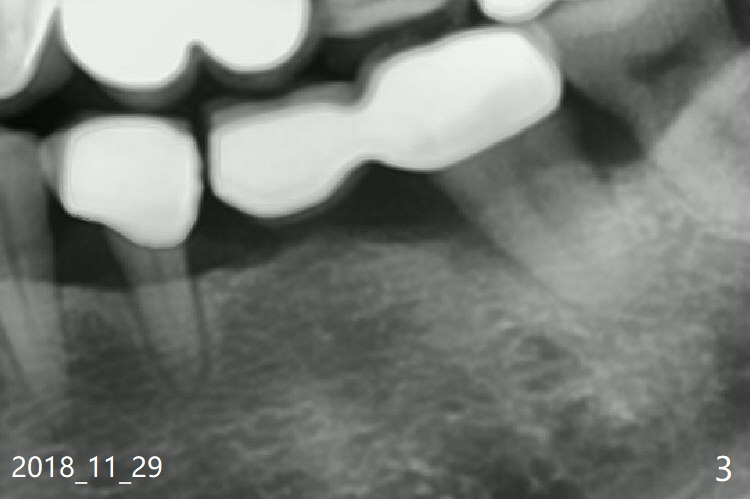

A 46-year-old woman had severe periodontal abscess lingual to #18-20 FPD a year ago (Fig.1,2 *). After SRP and Arestin placement #18 ML, the FPD was sectioned (Fig.2 >) to determine which abutment is to be extracted for implant. Since the sectioning, the patient has been unable to masticate on the left side (Fig.3). With removal of the FPD, CT is taken for surgical guide. Are the abutments salvageable (Fig.4,6)?